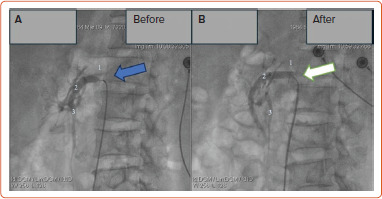

COVID-19 患者可能会出现急性肠系膜缺血。识别急性肠系膜缺血具有挑战性,尤其是最初的症状往往模糊不清,很容易被忽视。及早发现并立即干预以恢复血流,可以避免这些严重后果的发生。本报告介绍了两例严重急性呼吸综合征冠状病毒 2 感染后出现肠系膜上动脉(SMA)血栓形成的病例。CT 扫描显示两名患者均有肠系膜上动脉血栓形成,但无肠道坏死迹象。经血管造影确诊后,对患者进行了血管内介入治疗,并放置了自膨胀支架。随访6个月后,两名患者在接受双重抗血小板治疗后仍无症状。COVID-19 患者的非典型胃肠道表现应引起对不常见并发症(如 SMA 血栓形成)的怀疑。对于不伴有肠坏死的 SMA 闭塞,血管内治疗是一种可行的治疗方法。

COVID-19 patients may experience acute mesenteric ischaemia. Identifying acute mesenteric ischaemia is challenging, particularly as initial symptoms are often vague and easily overlooked. Early detection and immediate intervention to restore blood flow can prevent these severe consequences. Presented in this report are two cases of superior mesenteric artery (SMA) thrombosis following severe acute respiratory syndrome coronavirus 2 infection. CT scans demonstrated SMA thrombosis in both patients, with no evidence of bowel necrosis. Endovascular intervention with self-expanding stent placement was performed after angiographic confirmation of the diagnosis. At 6-month follow-up, both patients remained asymptomatic on dual antiplatelet therapy. Atypical gastrointestinal manifestations in COVID-19 patients should raise suspicion for uncommon complications, such as SMA thrombosis. For SMA occlusion without associated bowel necrosis, endovascular therapy represents a viable treatment approach.